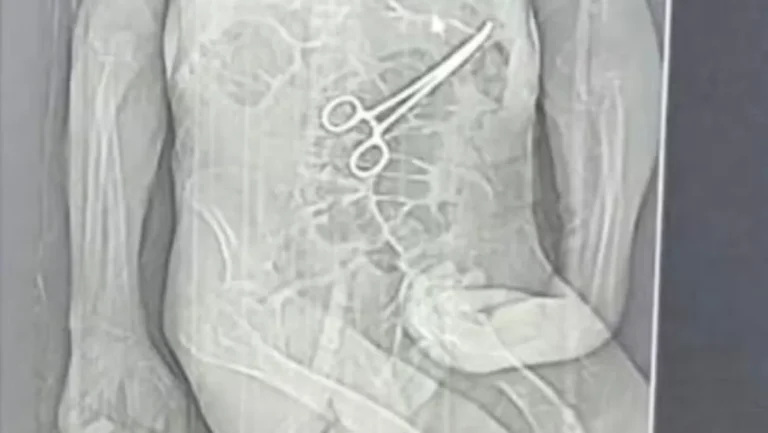

Investigação em MG: Idoso Morre Após Cirurgia com Instrumento Esquecido

A Secretaria de Saúde de João Pinheiro, localizada no Noroeste de Minas Gerais, instaurou uma sindicância para investigar a morte de um idoso que teve um instrumento cirúrgico deixado dentro de seu corpo durante uma cirurgia realizada em uma unidade de saúde local. O caso, que gerou grande comoção na comunidade, levanta sérias preocupações sobre a segurança nos procedimentos cirúrgicos.

O advogado da família de Manoel informou que ações legais foram iniciadas após a divulgação de um exame de tomografia, que revelou a presença do instrumento cirúrgico no corpo do paciente. Essa descoberta levantou sérias questões sobre a responsabilidade do hospital e os protocolos seguidos durante a cirurgia.

A família alega que a pinça cirúrgica foi esquecida dentro do corpo de Manoel após a primeira cirurgia, uma situação que, segundo eles, só foi confirmada após a morte do idoso. A Secretaria Municipal de Saúde de João Pinheiro confirmou que houve a retirada de um objeto durante a cirurgia, mas argumentou que Manoel estava em estado crítico e apresentava múltiplas comorbidades.